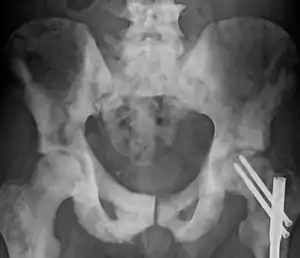

Diagram showing T1-3 stages of prostate cancer.

An important part of evaluating prostate cancer is determining the stage, or degree of spread. Knowing the stage helps define prognosis and is useful when selecting therapies.[158] The most common system is the four-stage TNM system (abbreviated from tumor/nodes/metastases). Its components include the size of the tumor, the number of involved lymph nodes, and the presence of any other metastases.[159]

The most important distinction made by any staging system is whether the cancer is confined to the prostate. In the TNM system, clinical T1 and T2 cancers are found only in the prostate, while T3 and T4 cancers have metastasized.[158] Several tests can be used to look for evidence of spread. Medical specialty professional organizations recommend against the use of PET scans, CT scans, or bone scans when a physician stages early prostate cancer with low risk for metastasis.[160] Those tests would be appropriate in cases such as when a CT scan evaluates spread within the pelvis, a bone scan looks for spread to the bones, and endorectal coil magnetic resonance imaging evaluates the prostatic capsule and the seminal vesicles. Bone scans should reveal osteoblastic appearance due to increased bone density in the areas of bone metastasis—the reverse of what is found in many other metastatic cancers.[161] Approved radiopharmaceutical diagnostic agents used in PET: fluciclovine (2016), Ga 68 PSMA-11 (2020), piflufolastat (2021).

After a biopsy, a pathologist examines the samples under a microscope. If cancer is present, the pathologist reports the grade of the tumor. The grade tells how much the tumor tissue differs from normal prostate tissue and suggests how fast the tumor is likely to grow. The pathologist assigns a Gleason number from 1 to 5 for the most common pattern observed under the microscope, then does the same for the second-most common pattern. The sum of these two numbers is the Gleason score. The Whitmore-Jewett stage is another method.